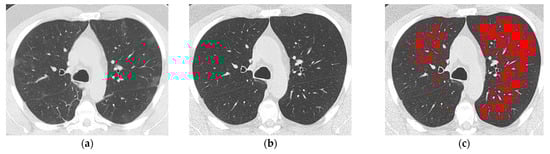

Figure 2.

A 55-year-old never-smoker man with COVID-19 pneumonia detected in March 2020. The baseline axial high-resolution computed tomography (HRCT) image at the level of the aortic arch (a) was typical for COVID-19 pneumonia and characterized mainly by bilateral ground-glass opacities, which extended to 20% of the whole lung parenchyma (visual score). The axial follow-up HRCT image at the same level performed 30 months later (b) identified complete resolution of COVID-19 pneumonia without emphysema at visual assessment. (c) The same axial HRCT in (b) with highlighted in red low attenuation areas (LAAs) identified by software analysis showed 20% %LAAs extent relative to the whole lung volume; pulmonary function tests performed 7 days before follow-up HRCT showed a reduced %DLCO (49%).